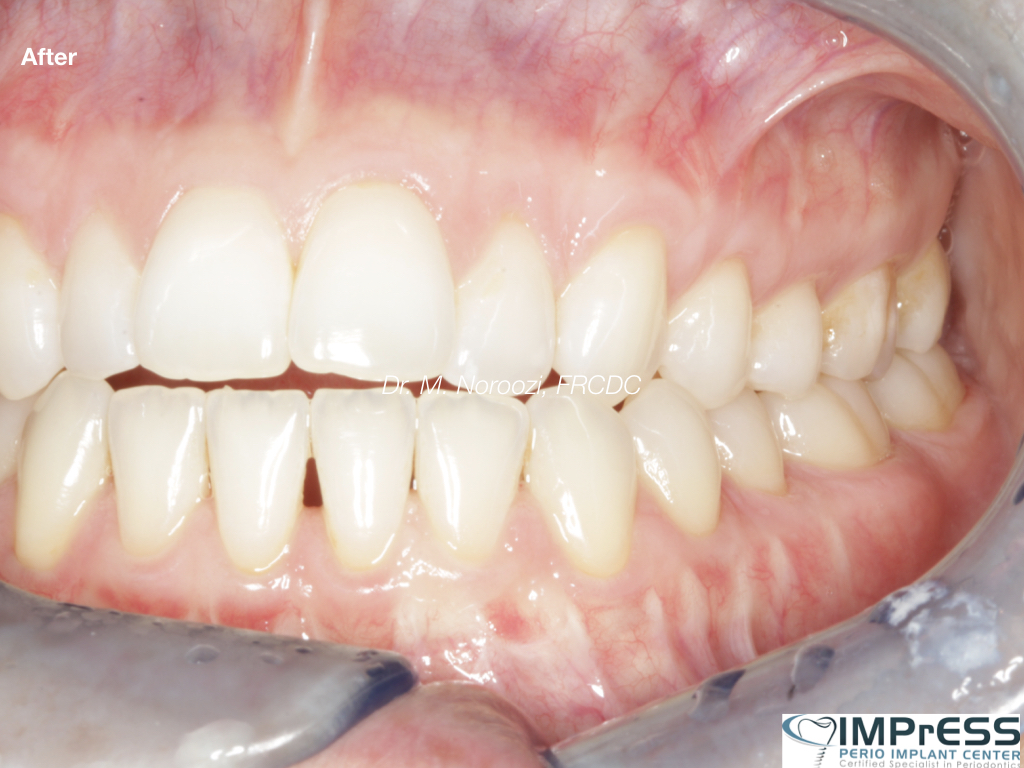

Full Mouth Reconstruction with Fixed Implant Bridge – All on X

All on X implant Full Mouth Implant Reconstruction All on 4 Implants IMPrESS Perio Implant Center Vancouver Burnaby Periodontist Prosthodontist Implant Specialist Dr. Noroozi Periodontist Implant Specialist

mile Makeover with Full Mouth Implants IMPrESS Perio Implant Center Burnaby BC Dr Noroozi

Full Mouth Implant Rehabilitation IMPrESS Perio Implant Center Dr. Noroozi implant Specialist Burnaby Vancouver BC

All On X Full Mouth Implants Fixed Teeth IMPrESS Perio Implant Centre Dr Noroozi Burnaby Vancouver BC

All on X Full Mouth Implant Rehabilitation IMPrESS Perio Implant Center Dr. Noroozi Implant Specialist Burnaby

All on X implant Full Mouth Implant Reconstruction All on 4 Implants IMPrESS Perio Implant Center Vancouver Burnaby Periodontist

Full Mouth Implant Restoration Burnaby Implant Specialist IMPrESS Perio Implant Center Dr. Noroozi

Full Mouth Implants IMPrESS Perio Implant Center Burnaby Vancouver BC Dr. Noroozi All On 4 Implants